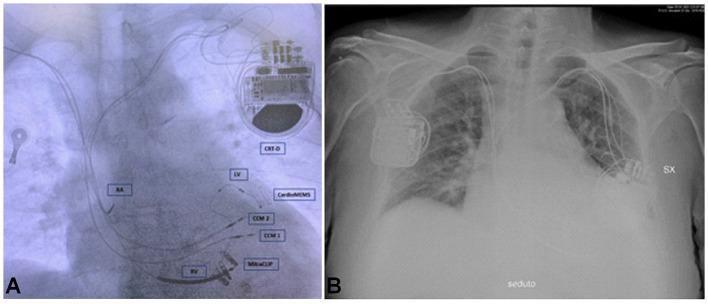

During the last years, the management of heart failure (HF) made substantial progress, focusing on device-based therapies to meet the demands of this complex syndrome. In this case report, we present a multistep approach to deal with HF. Specifically, we report the first patient subjected to the implantation of both Optimizer Smart (Impulse Dynamics Inc., Marlton, NJ, USA) and CardioMEMS devices. A 72-year-old male patient with HF and reduced ejection fraction (HFrEF) was admitted to our cardiology department in January 2021, following a progressive shortening of the time between hospitalizations for levosimendan infusions. Specifically, the patient was monitored daily by CardioMEMS, and a strategy of levosimendan infusions guided by the device had been adopted. He was also a carrier of MitraClips and cardiac resynchronization therapy defibrillator (CRT-D) and had optimized HF medical therapy. In January 2021, the patient implanted Optimizer Smart device for cardiac contractility modulation (CCM) therapy because of poor response to therapy and elevated pulmonary artery pressure (PAP). CCM significantly reduced PAP values following discharge (systolic PAP 33.67 ± 2.92 vs. 40.6 ± 3.37 mmHg, diastolic PAP 14.5 ± 2.01 vs. 22.5 ± 2.53 mmHg, mean PAP 22.87 ± 2.20 vs. 30.9 ± 2.99 mmHg, HR 60.93 ± 1.53 vs. 80.83 ± 3.66 bpm; < 0.0001), with persisting effect at 9 months. The usefulness of CCM is objectively demonstrated for the first time by continuous invasive monitoring of PAP by CardioMEMS, which can suggest the correct timing for CCM implantation.

在过去几年中,心力衰竭(HF)的管理取得了重大进展,重点是基于设备的治疗方法,以满足这种复杂综合征的需求。在本病例报告中,我们展示了一种处理HF的多步骤方法。具体而言,我们报告了首例同时植入Optimizer Smart(美国新泽西州马尔顿市脉冲动力公司)和CardioMEMS设备的患者。一名72岁男性HF患者,射血分数降低(HFrEF),因左西孟旦输注住院间隔时间逐渐缩短,于2021年1月入住我院心内科。具体来说,该患者每天由CardioMEMS进行监测,并采用了由该设备指导的左西孟旦输注策略。他还植入了MitraClips和心脏再同步化治疗除颤器(CRT-D),并接受了优化的HF药物治疗。2021年1月,由于对治疗反应不佳且肺动脉压(PAP)升高,该患者植入了Optimizer Smart设备进行心脏收缩力调制(CCM)治疗。出院后CCM显著降低了PAP值(收缩期PAP:33.67±2.92 vs. 40.6±3.37 mmHg,舒张期PAP:14.5±2.01 vs. 22.5±2.53 mmHg,平均PAP:22.87±2.20 vs. 30.9±2.99 mmHg,心率:60.93±1.53 vs. 80.83±3.66次/分钟;P<0.0001),且在9个月时仍有持续效果。CardioMEMS对PAP的连续有创监测首次客观证明了CCM的有效性,这可以提示CCM植入的正确时机。